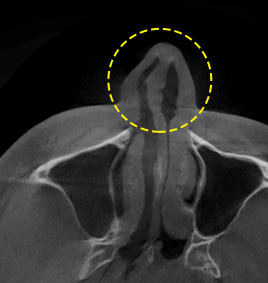

3D-CT nose surgery involves identifying not only the external parts of the nose but also symptoms and causes of nasal bone, crooked nose, nasal septal cartilage, nasal congestion, etc. As three-dimensional analysis using 3D-CT helps establish an adequate surgery plan and reduce damage to blood vessels and nerves, safe and precise operation can be performed.

3D-CT analyzes the nose three-dimensionally.

FACE uses advanced 3D-CT equipment to analyze the overall condition of nasal bone, nasal septal cartilage, skin tissue, asymmetry, etc.,

which cannot be identified by general consultation,

in order to secure safer and more precise nose surgery.